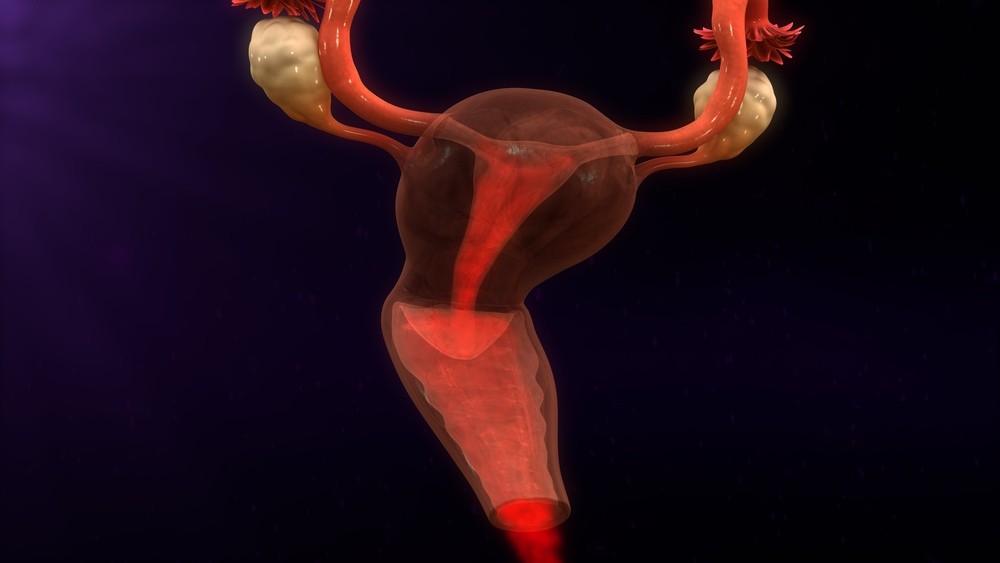

Анатомия женского организма: строение и функции матки

Раздел: Фотопуть к знанию